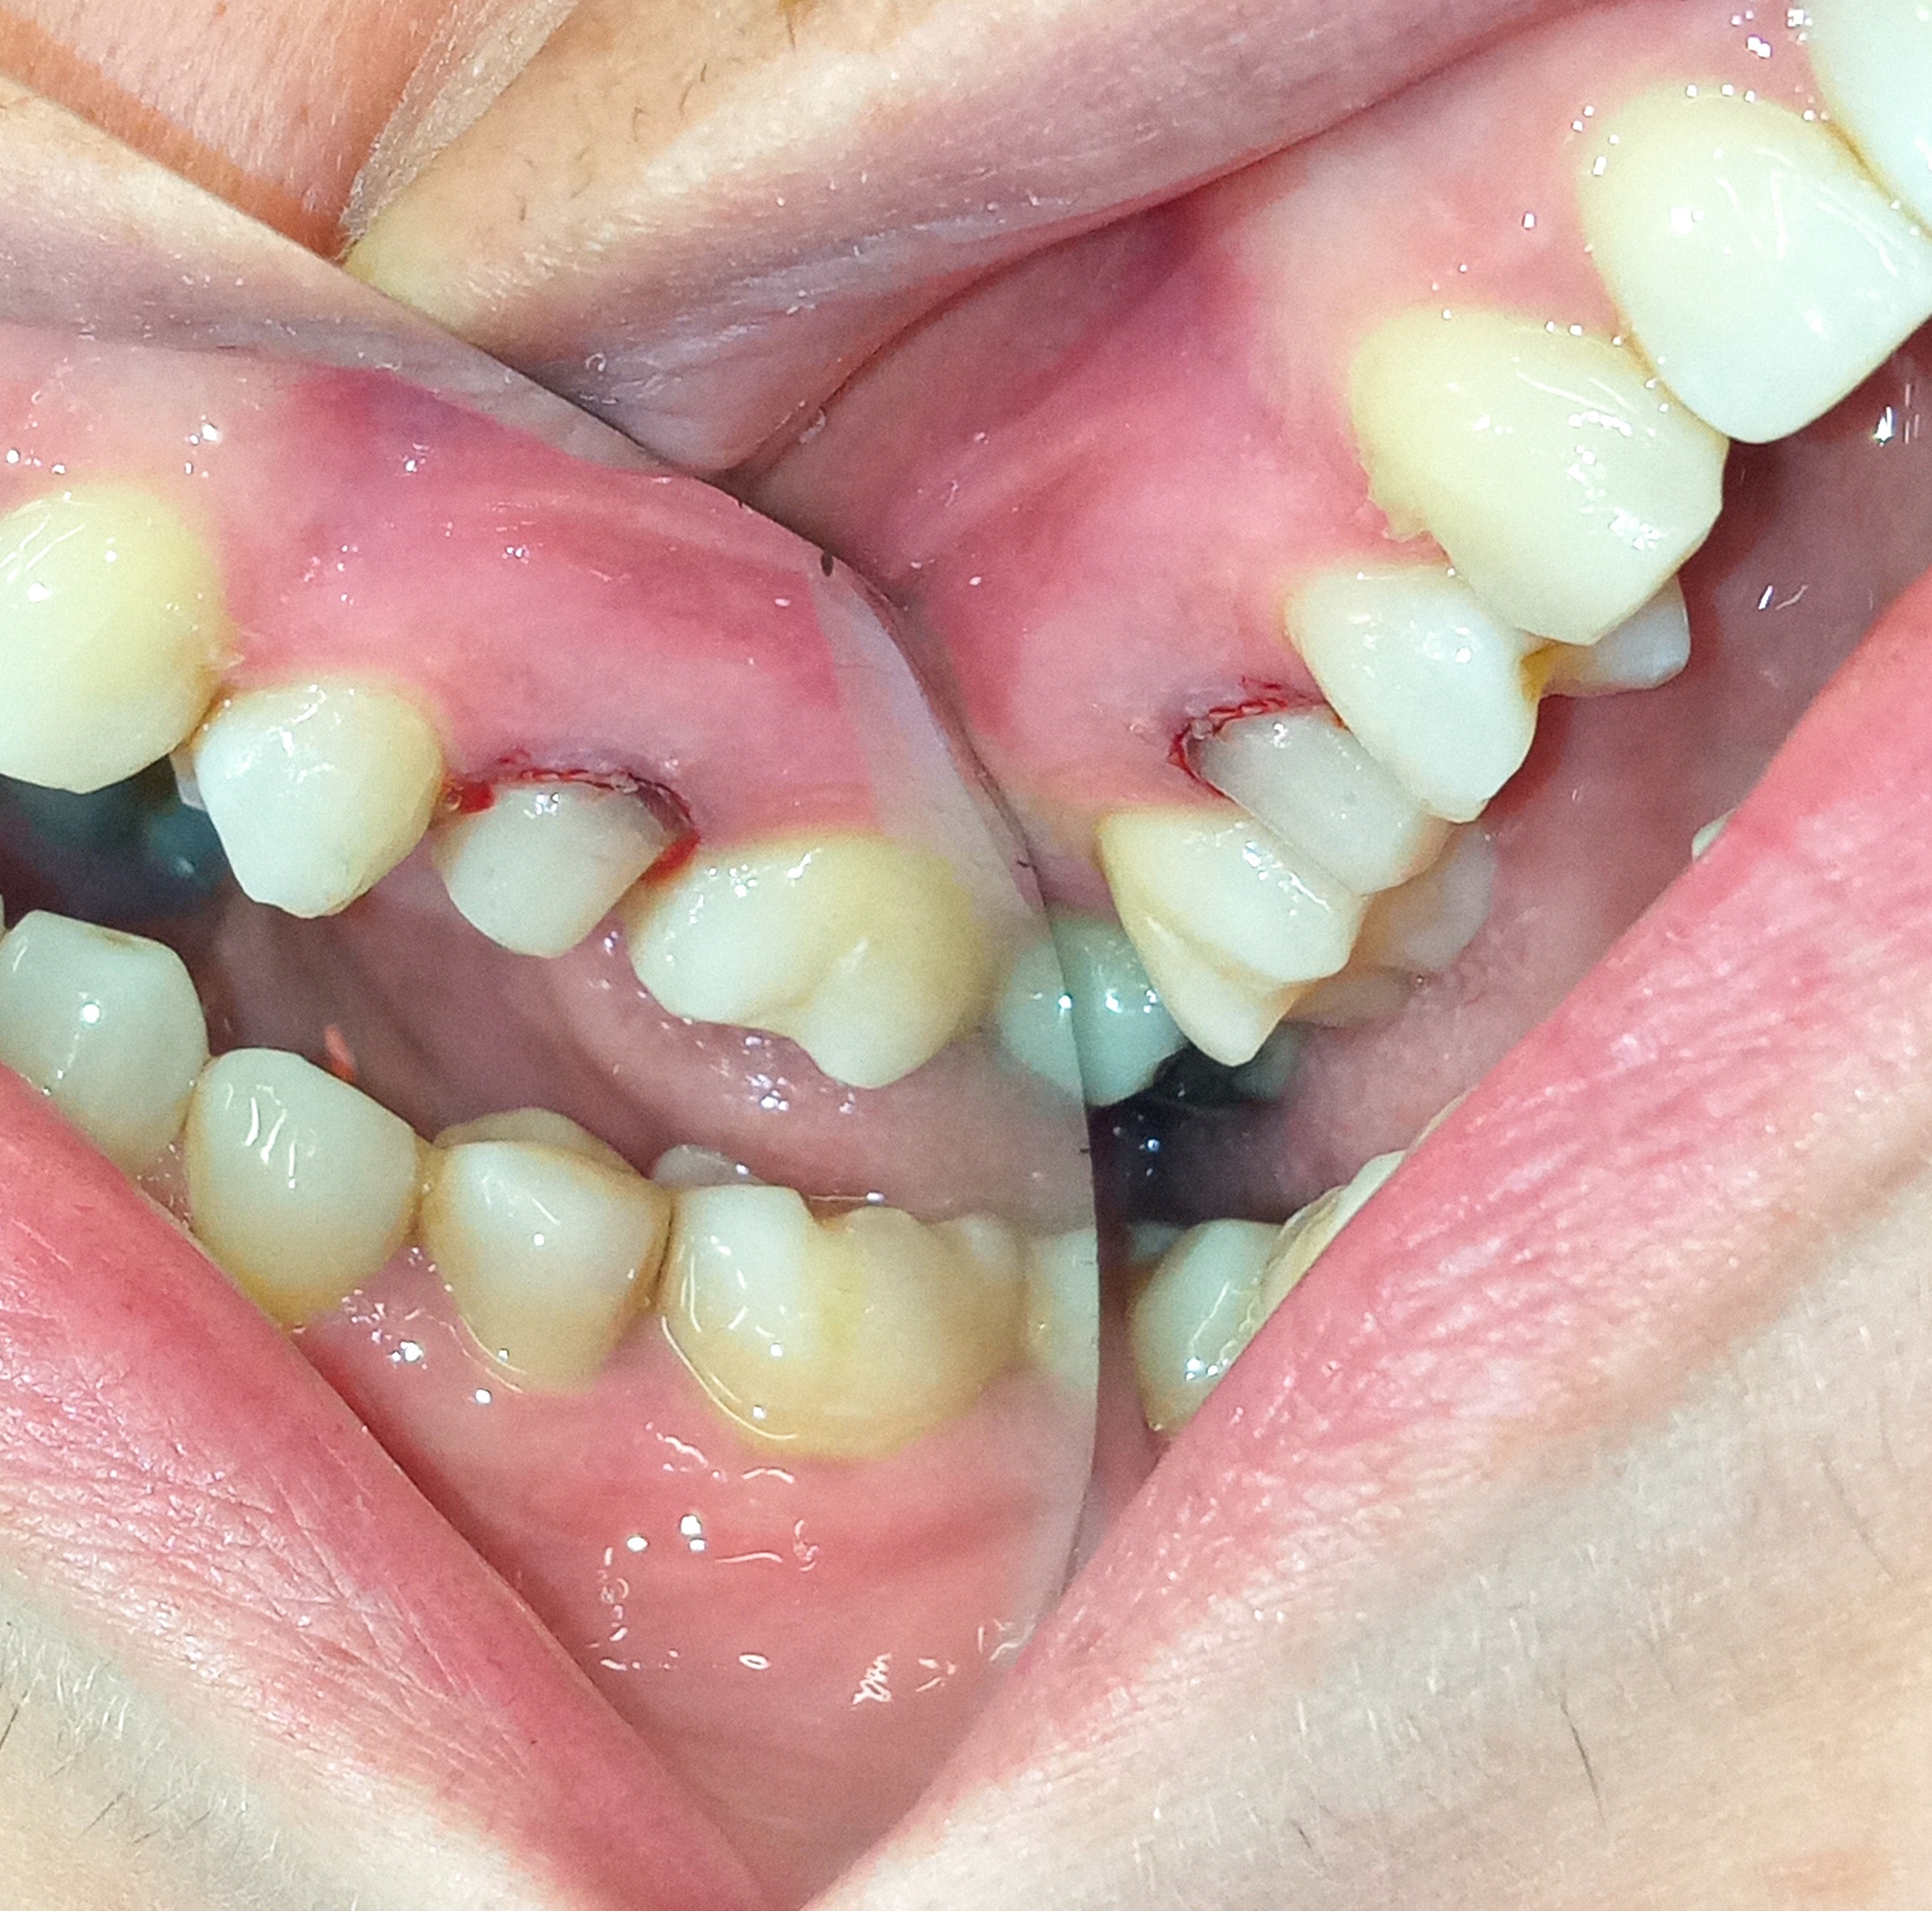

Αρχική κλινική εικόνα του μεγάλου οδοντικού ελλείμματος